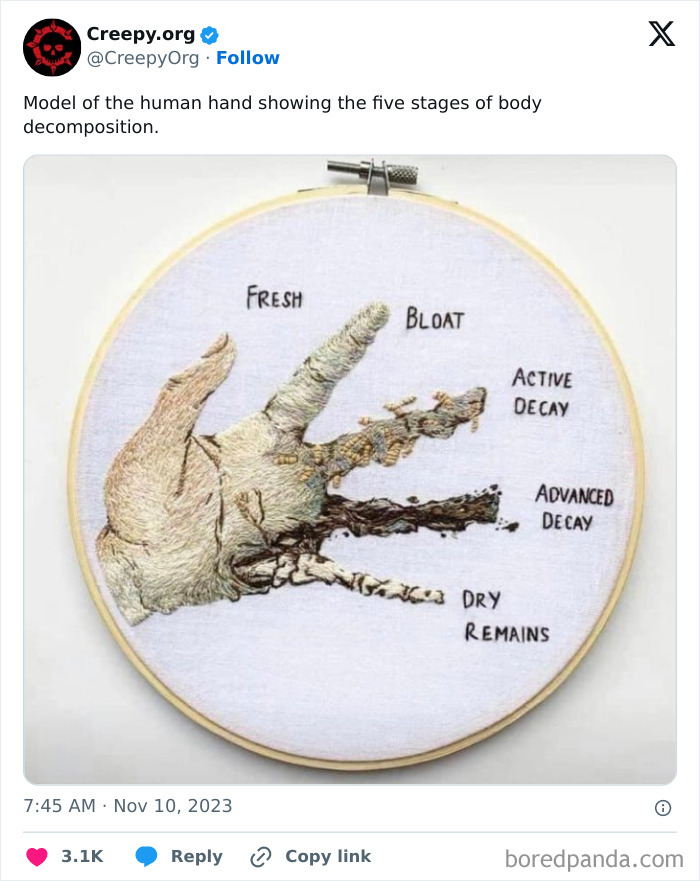

#2

Image credits: CreepyOrg